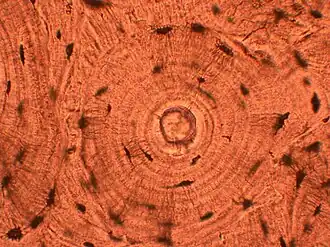

Whorled: Multiple concentric objects, or spiral-shaped -

Cartwheel pattern: Center points that radiate cells or connective tissue outward